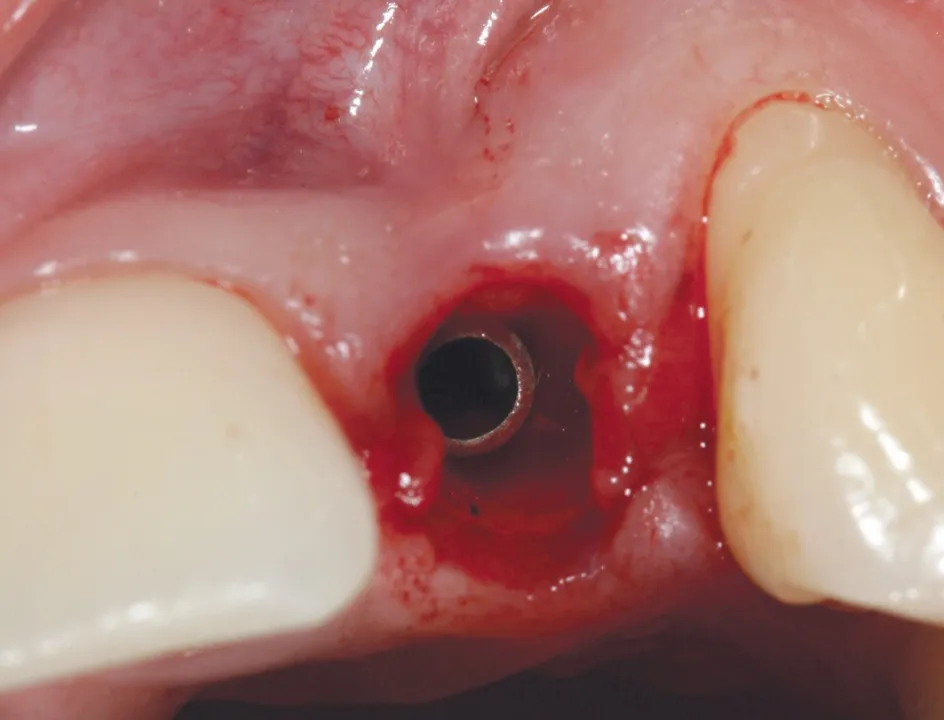

2 号病例 - Patrick EXBRAYAT 医生(图 21 至 35)

22 岁患者,23 异位,行正颌外科种植术后 22 出现严重根吸收。

图 24 :植入 Axiom® 2.8 x 14 种植体。

图 25 :种植体就位。

图 26 :术后 X 线检查。